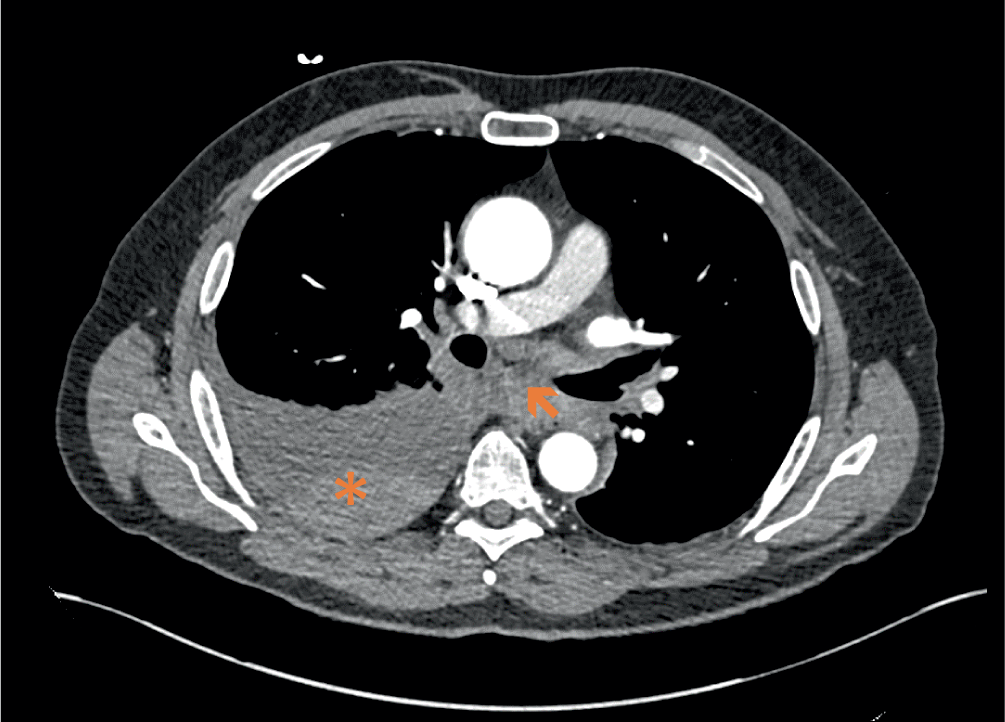

Bei Übergabe in der Notaufnahme präsentierte sich der Patient wach, 4‑fach orientiert und in einem regelrechten Allgemein- und Ernährungszustand. Der Patient gab an, nun keinerlei Beschwerden mehr zu haben. Die Vitalparameter lagen bis auf eine leicht erhöhte Atemfrequenz (25/min) im Normbereich. Rechts basal fand sich ein abgeschwächtes Atemgeräusch, die weitere körperliche Untersuchung war unauffällig. Im EKG zeigte sich ein normofrequenter Sinusrhythmus ohne akute Erregungsrückbildungsstörungen. Im Point-of-Care-Ultraschall konnte ein rechtsseitiger Pleuraerguss mit einer maximalen kraniokaudalen Ausdehnung von ca. 6 cm festgestellt werden. Laborchemisch waren die D‑Dimere leichtgradig erhöht (0,77 mg/l [< 0,5 mg/l]). Die weiteren Gerinnungsparameter, die Entzündungswerte und kardialen Markerenzyme waren normwertig. Zur weiteren Diagnostik erfolgte eine kontrastmittelgestützte CT-Untersuchung des Thorax (Abb. 1). Dabei fanden sich der rechtsseitige Pleuraerguss mit erhöhten Dichtewerten sowie eine Wandverdickung des distalen Ösophagus. Eine Lungenarterienembolie, ein Aortenaneurysma oder eine Aortendissektion konnten ausgeschlossen werden. Zur weiteren Abklärung erfolgte eine Pleurapunktion, wobei sich im Pleurapunktat ein Hämoglobinwert von 8,1 g/dl fand.

Abb. 1

CT Thorax mit Darstellung des Hämatothorax rechts (Asterisk) und des wandverdickten distalen Ösophagus (Pfeil)